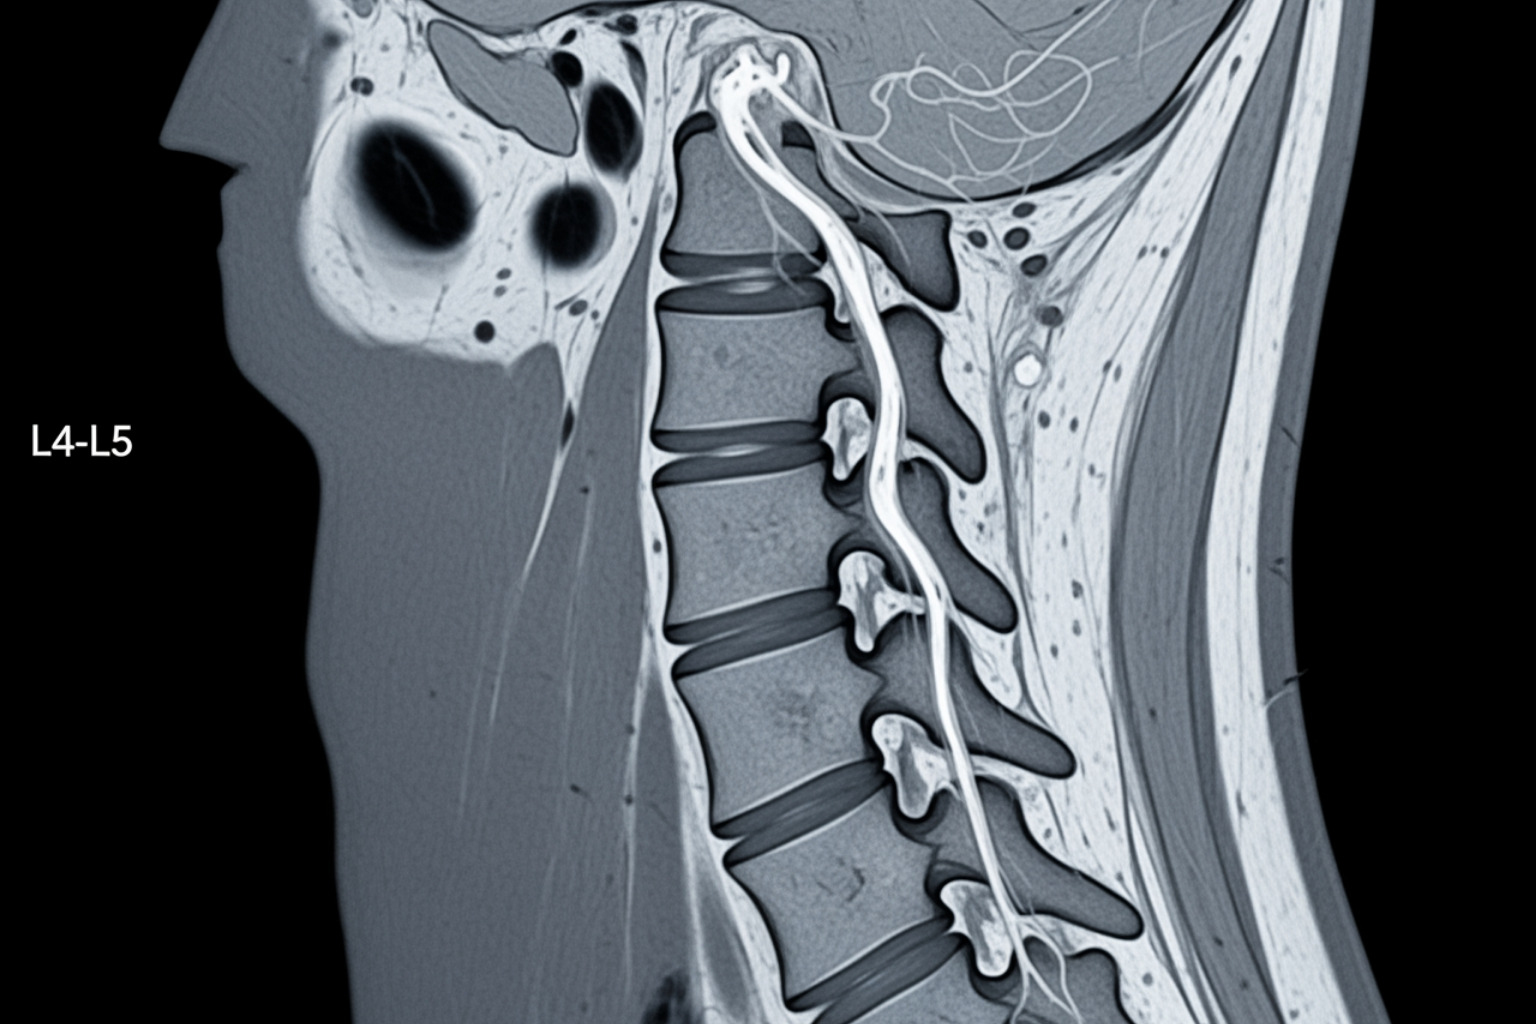

To get a clearer picture, imaging tests may be used:

- X-rays show bone issues like spurs or alignment problems but not soft tissues.

- An MRI (Magnetic Resonance Imaging) provides a detailed view of soft tissues, showing herniated discs, stenosis, and nerve compression.

- CT scans (Computed Tomography) offer detailed images of bone structures and can also reveal disc problems.

- Electromyography (EMG) and Nerve Conduction Studies (NCS) measure nerve and muscle electrical activity to pinpoint nerve damage and its severity.